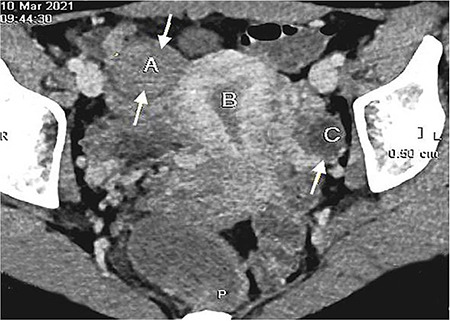

Hemangioma in female reproductive organs, particularly in the fallopian tube (FT), is a sporadic disease. In this report, we describe a case of hidden capillary hemangioma in FT in a 39-year-old woman who suffered from uterine leiomyoma. During the preoperative stage, pelvic sonography, computed tomography, and diagnostic laparoscopy revealed a subserous leiomyomatous nodule located along the posterior wall of the uterus. Despite this, intraoperatively, a benign vascular neoplasm was diagnosed. Histologically, it is characterized by multiple thin-walled vascular spaces lined with a single layer of endothelial cells, in which single mitoses were observed. The diagnosis was then confirmed immunohistochemically by CD31 and CD34 expression in the endothelial cells lining the inner surface of the spaces and the low mitotic activity of the tumor cells. It is virtually impossible to diagnose this asymptomatic neoplasm before and during surgery, which can result in an inadequate number of surgeries. Incorrect interpretation of a benign tumor at a young age can lead to unnecessary radical surgery with a resulting loss of fertility, and an unrevealed malignant process can threaten life.